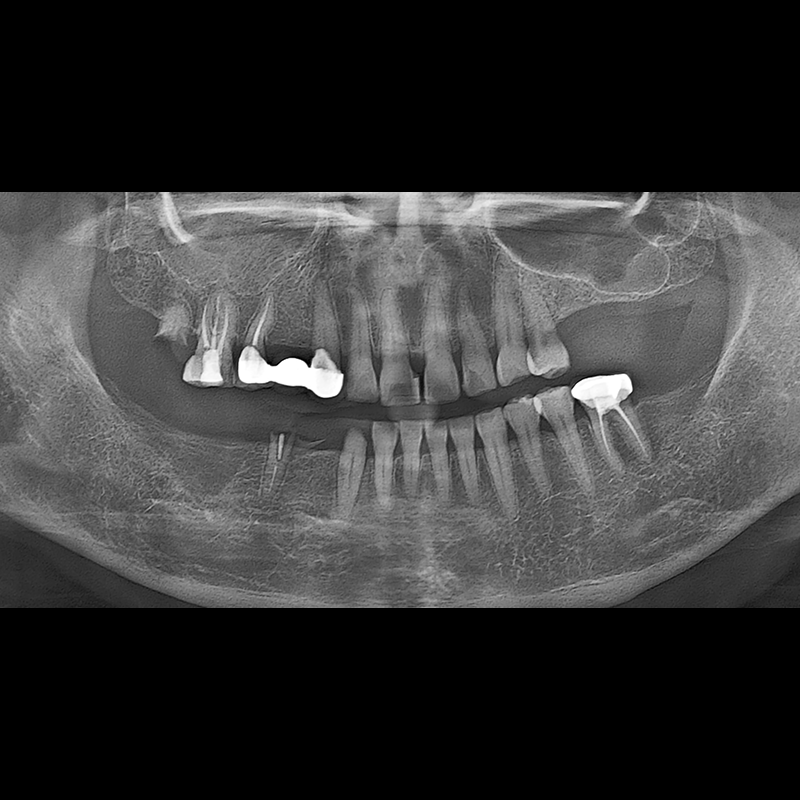

IMPLANT

BEFORE AFTER

Implant before and after 2025.05.30

Implants were placed in the missing tooth and in the tooth position where it was difficult to save.